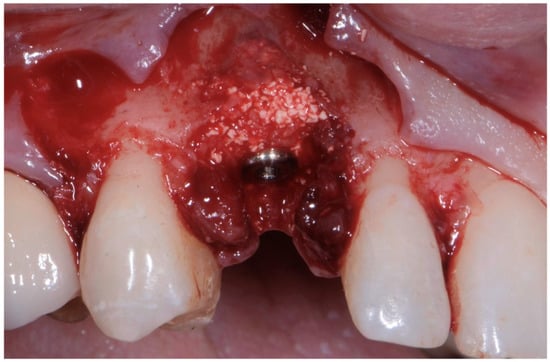

As already evaluated during software planning, after implant insertion, a buccal bone dehiscence of 2 mm occurred. The remaining buccal bone thickness was less than 1 mm. A mixture of biomaterial (Cerabone; Botiss) and autologous bone was placed to cover the exposed implant threads and the thin layer of remaining buccal bone and to fill the gap between the implant surface and the socket wall (Figure 7). Bone filler material should be limited to the rough implant surface, extending as little as possible to the transmucosal collar; however, the biomaterial positioning should be slightly in excess to avoid the loss of biomaterial during the following phase. If there is still an excess, it should be removed just before the very last suture. The biomaterial was then stabilized using a thin pericardium membrane (Jason Membrane; Botiss) placed between the bone particles and a connective-tissue graft (Figure 8a,b). The pericardium membrane was sutured to the periosteum left appositively laterally to the membrane.

Figure 7. Biomaterial and autologous bone placed to cover the exposed implant threads and to fill the gap between implant surface and socket wall.